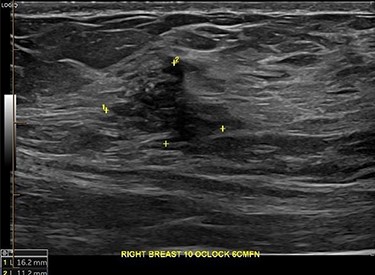

An ultrasound of the left breast demonstrated a 60-mm irregularity with no underlying collection at the 10 O’clock position, 2 cm from the nipple (Fig. 1). AB was treated with 5 days of oral flucloxacillin for presumed mastitis, and underwent a bilateral mammogram and ultrasound due to the suspicious irregularity of the left breast lesion. This showed an area of asymmetric density in the medial left breast with hyperemia (Fig. 2). The right breast showed two clusters of pleomorphic microcalcifications in the upper outer quadrant, further characterized as irregular lesions measuring 16 × 11 × 11 mm and 9 × 10 × 7 mm (Fig. 3).